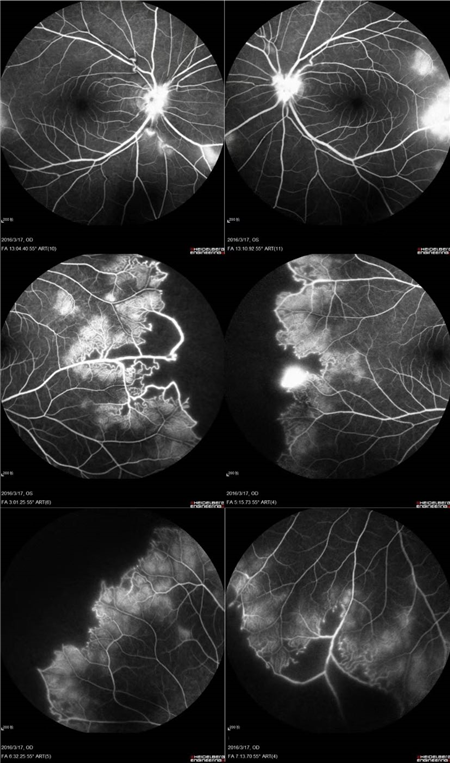

视盘附近的动脉和动脉分叉处出现瘤样动脉扩张,视盘充血,边界不清,引起视盘周围视网膜内硬性渗出;视盘周可有少量放射状出血。

静脉不规则扩张和血管鞘膜,周边部小血管广泛闭塞,交界处毛细血管扩张和异常吻合。

严重者可发生从周边到黄斑的血管闭塞和缺血、玻血、新生血管性青光眼,最终视神经萎缩。

长期追踪发现动脉瘤是一种血管炎性的游走性改变,炎症消失时,血管壁强度恢复,瘤体减小,甚至恢复正常。